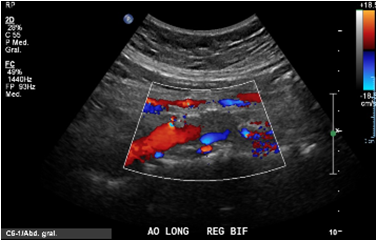

Caso de Oclusión de aorta abdominal distal, con presencial de colaterales y alteración de curvas arteriales hacia EEII.

Se observa segmento oclusivo a nivel de la aorta abdominal (de 3 cm aprox.) previo a la bifurcación de las iliacas, con contenido ecogénico y ateromatosis cálcica asociada, sin flujo a este nivel.

Hay evidencia de colaterales de alta velocidad circundante a la oclusión que recanalizan el origen de ambas arterias iliacas comunes.

Se observan curvas monofásicas de baja resistencia con pérdida de componente reverso diastólico y disminución de la velocidad sistólica en todo el árbol arterial de ambas extremidades inferiores. En la aorta abdominal distal, a 3 cm de la bifurcación, se observa un segmento oclusivo de la aorta con contenido ecogénico calcificado, sin flujo a este nivel. Previo a la oclusión se observa curva pre oclusiva monofásica de baja velocidad. Se observa flujo colateral paralelo a la oclusión que reconstituye el flujo en el origen de las arterias iliacas comunes, observándose flujos monofásicos hacia distal con reducción en aproximadamente un 60%